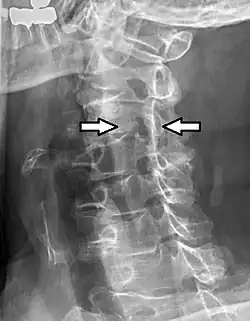

- Projectional radiograph of a man presenting with pain by the nape and left shoulder, showing a stenosis in the intervertebral foramen of cervical spinal nerve 4, corresponding with the affected dermatome.